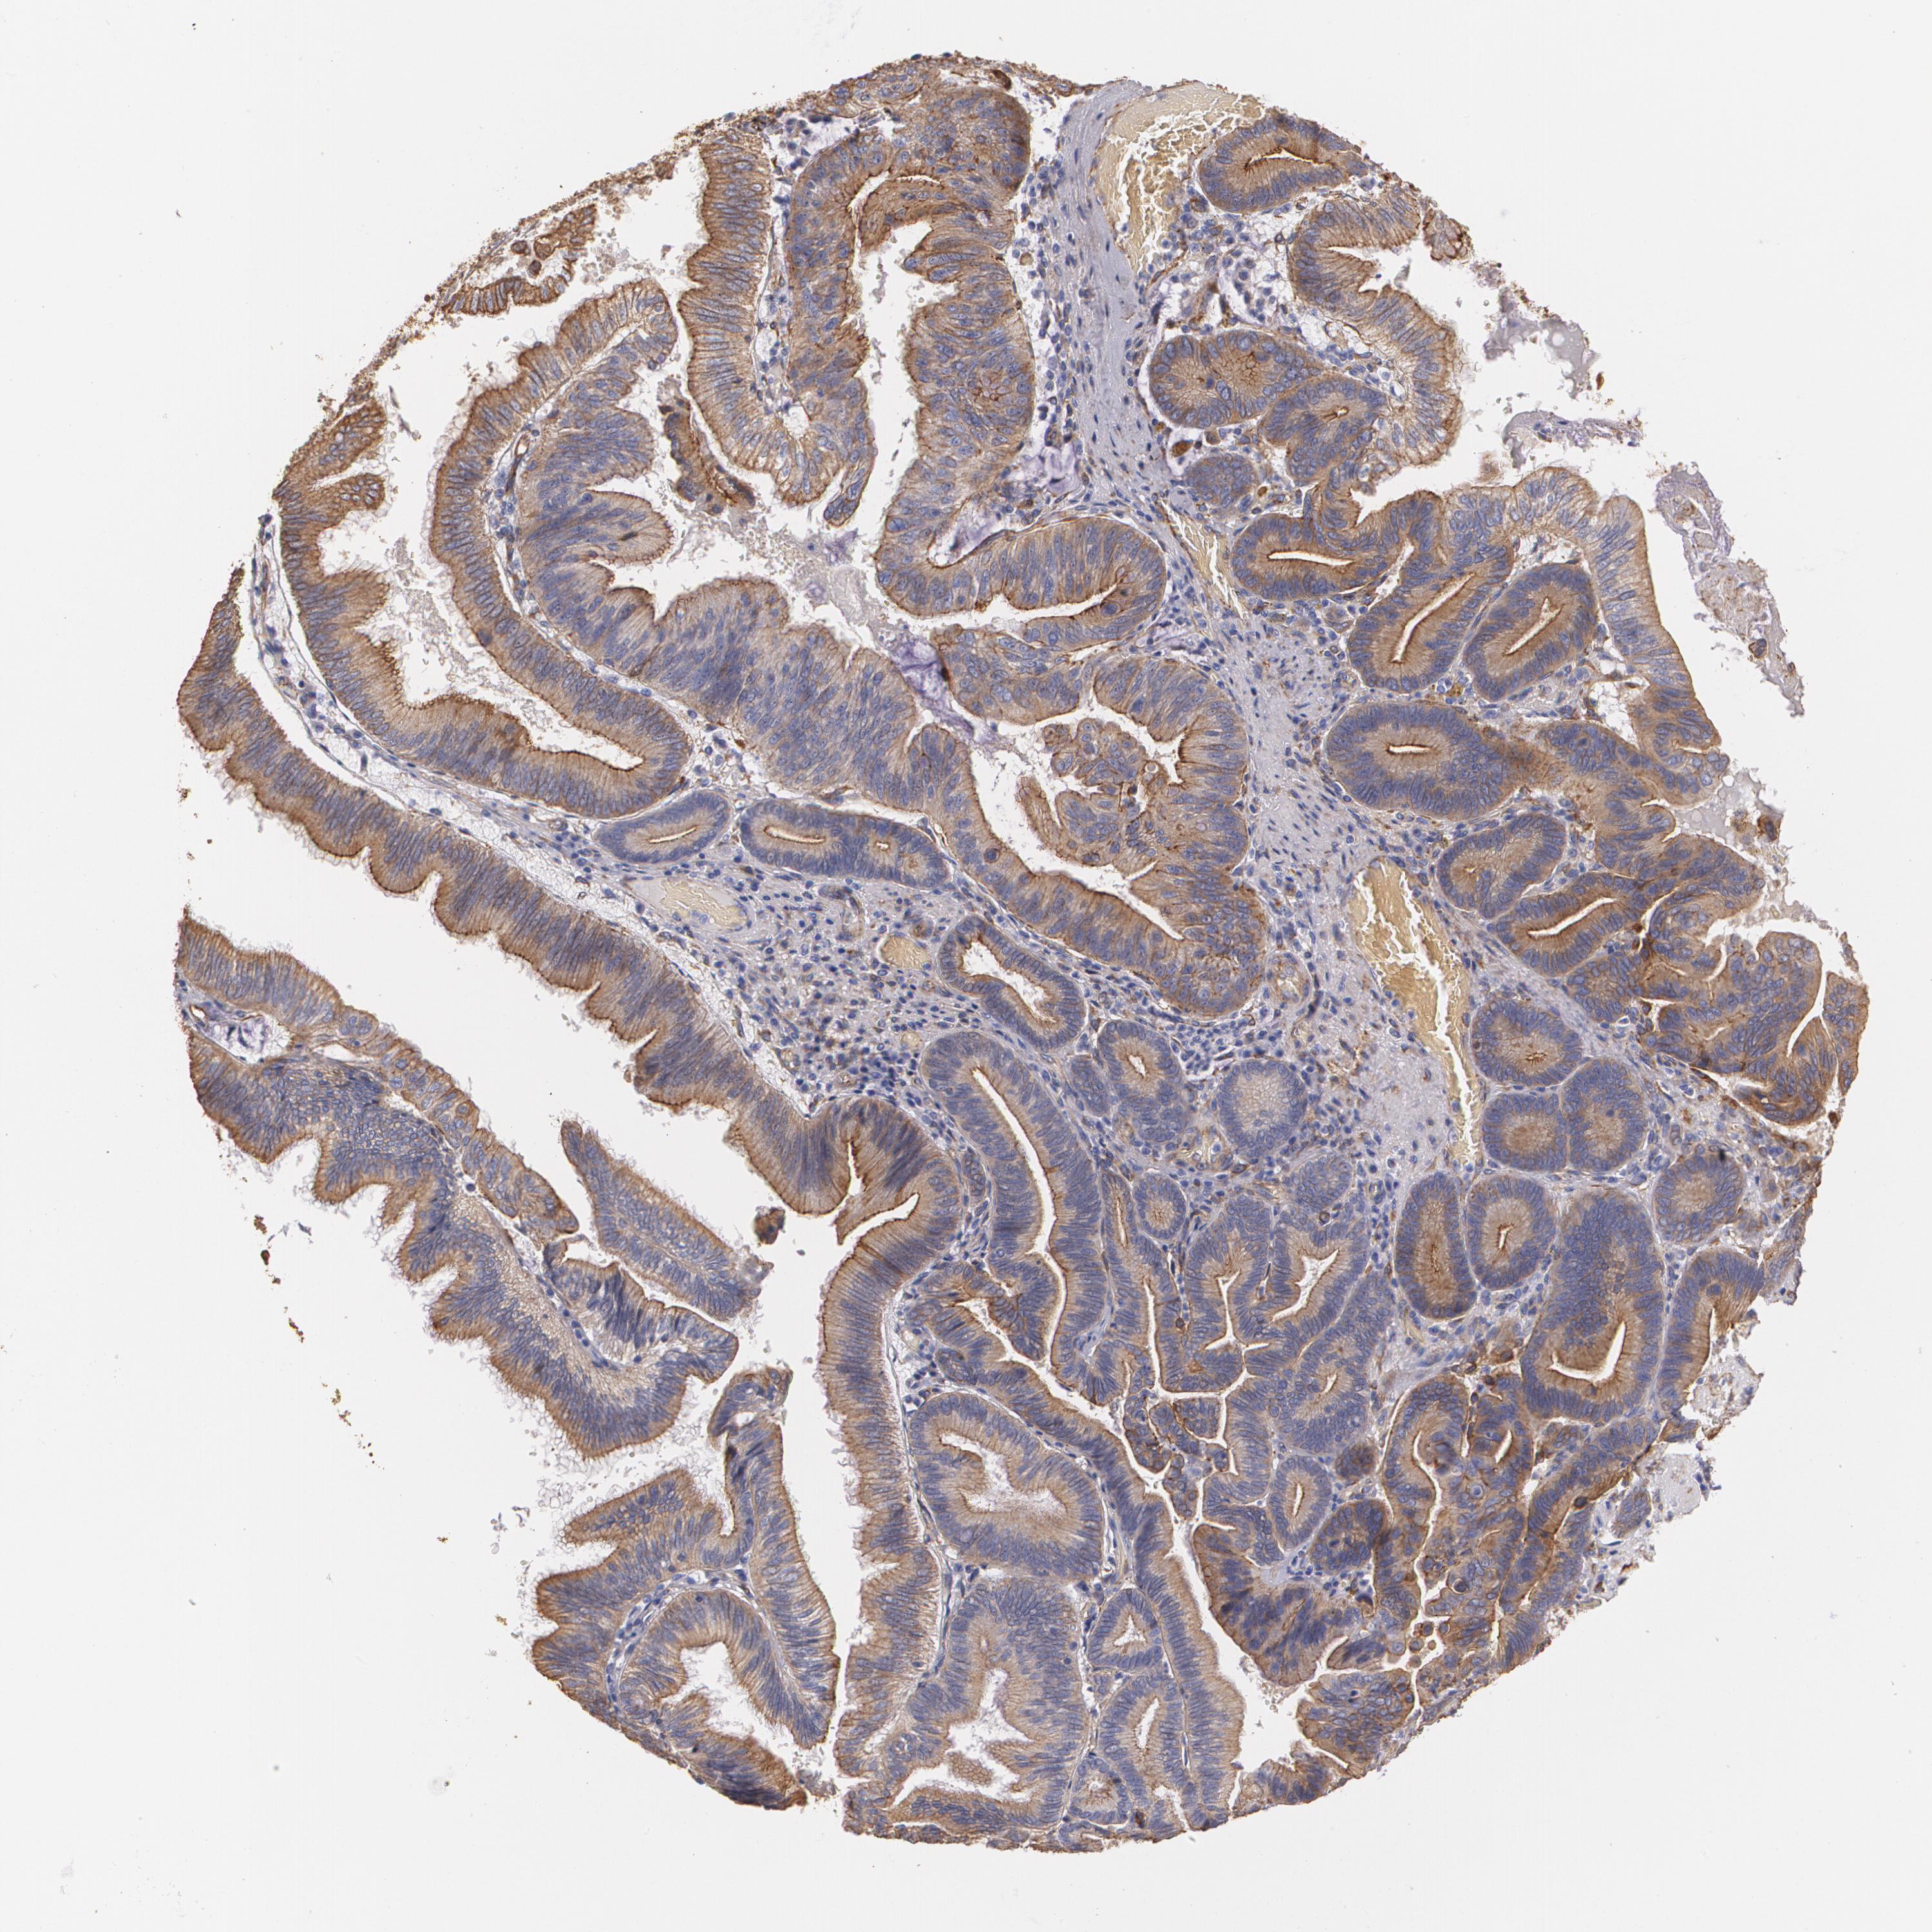

PANCREATIC CANCER - Protein expressioni

A mouse-over function shows sample information and annotation data. Click on an image to view it in a full screen mode. Samples can be filtered based on level of antibody staining by selecting one or several of the following categories: high, medium, low and not detected. The assay and annotation is described here.

Note that samples used for immunohistochemistry by the Human Protein Atlas do not correspond to samples in the TCGA dataset.

Antibody stainingi

Antibody staining in the annotated cell types in the current human tissue is reported as not detected, low, medium, or high, based on conventional immunohistochemistry profiling in selected tissues. This score is based on the combination of the staining intensity and fraction of stained cells.

Each image is clickable and will lead to virtual microscopy that enables deeper exploration of all samples and also displays staining intensity scores, fraction scores and subcellular localization as well as patient and tissue information for each sample.

Antibody HPA001636

Antibody HPA001637

Antibody CAB010822

Staining

High

Medium

Low

Not detected

Intensity

Strong

Moderate

Weak

Negative

Quantity

>75%

75%-25%

<25%

None

Location

Nuclear

Cytoplasmic/membranous

Cytoplasmic/membranous,nuclear

Adenocarcinoma, NOS

Adenocarcinoma, metastatic, NOS